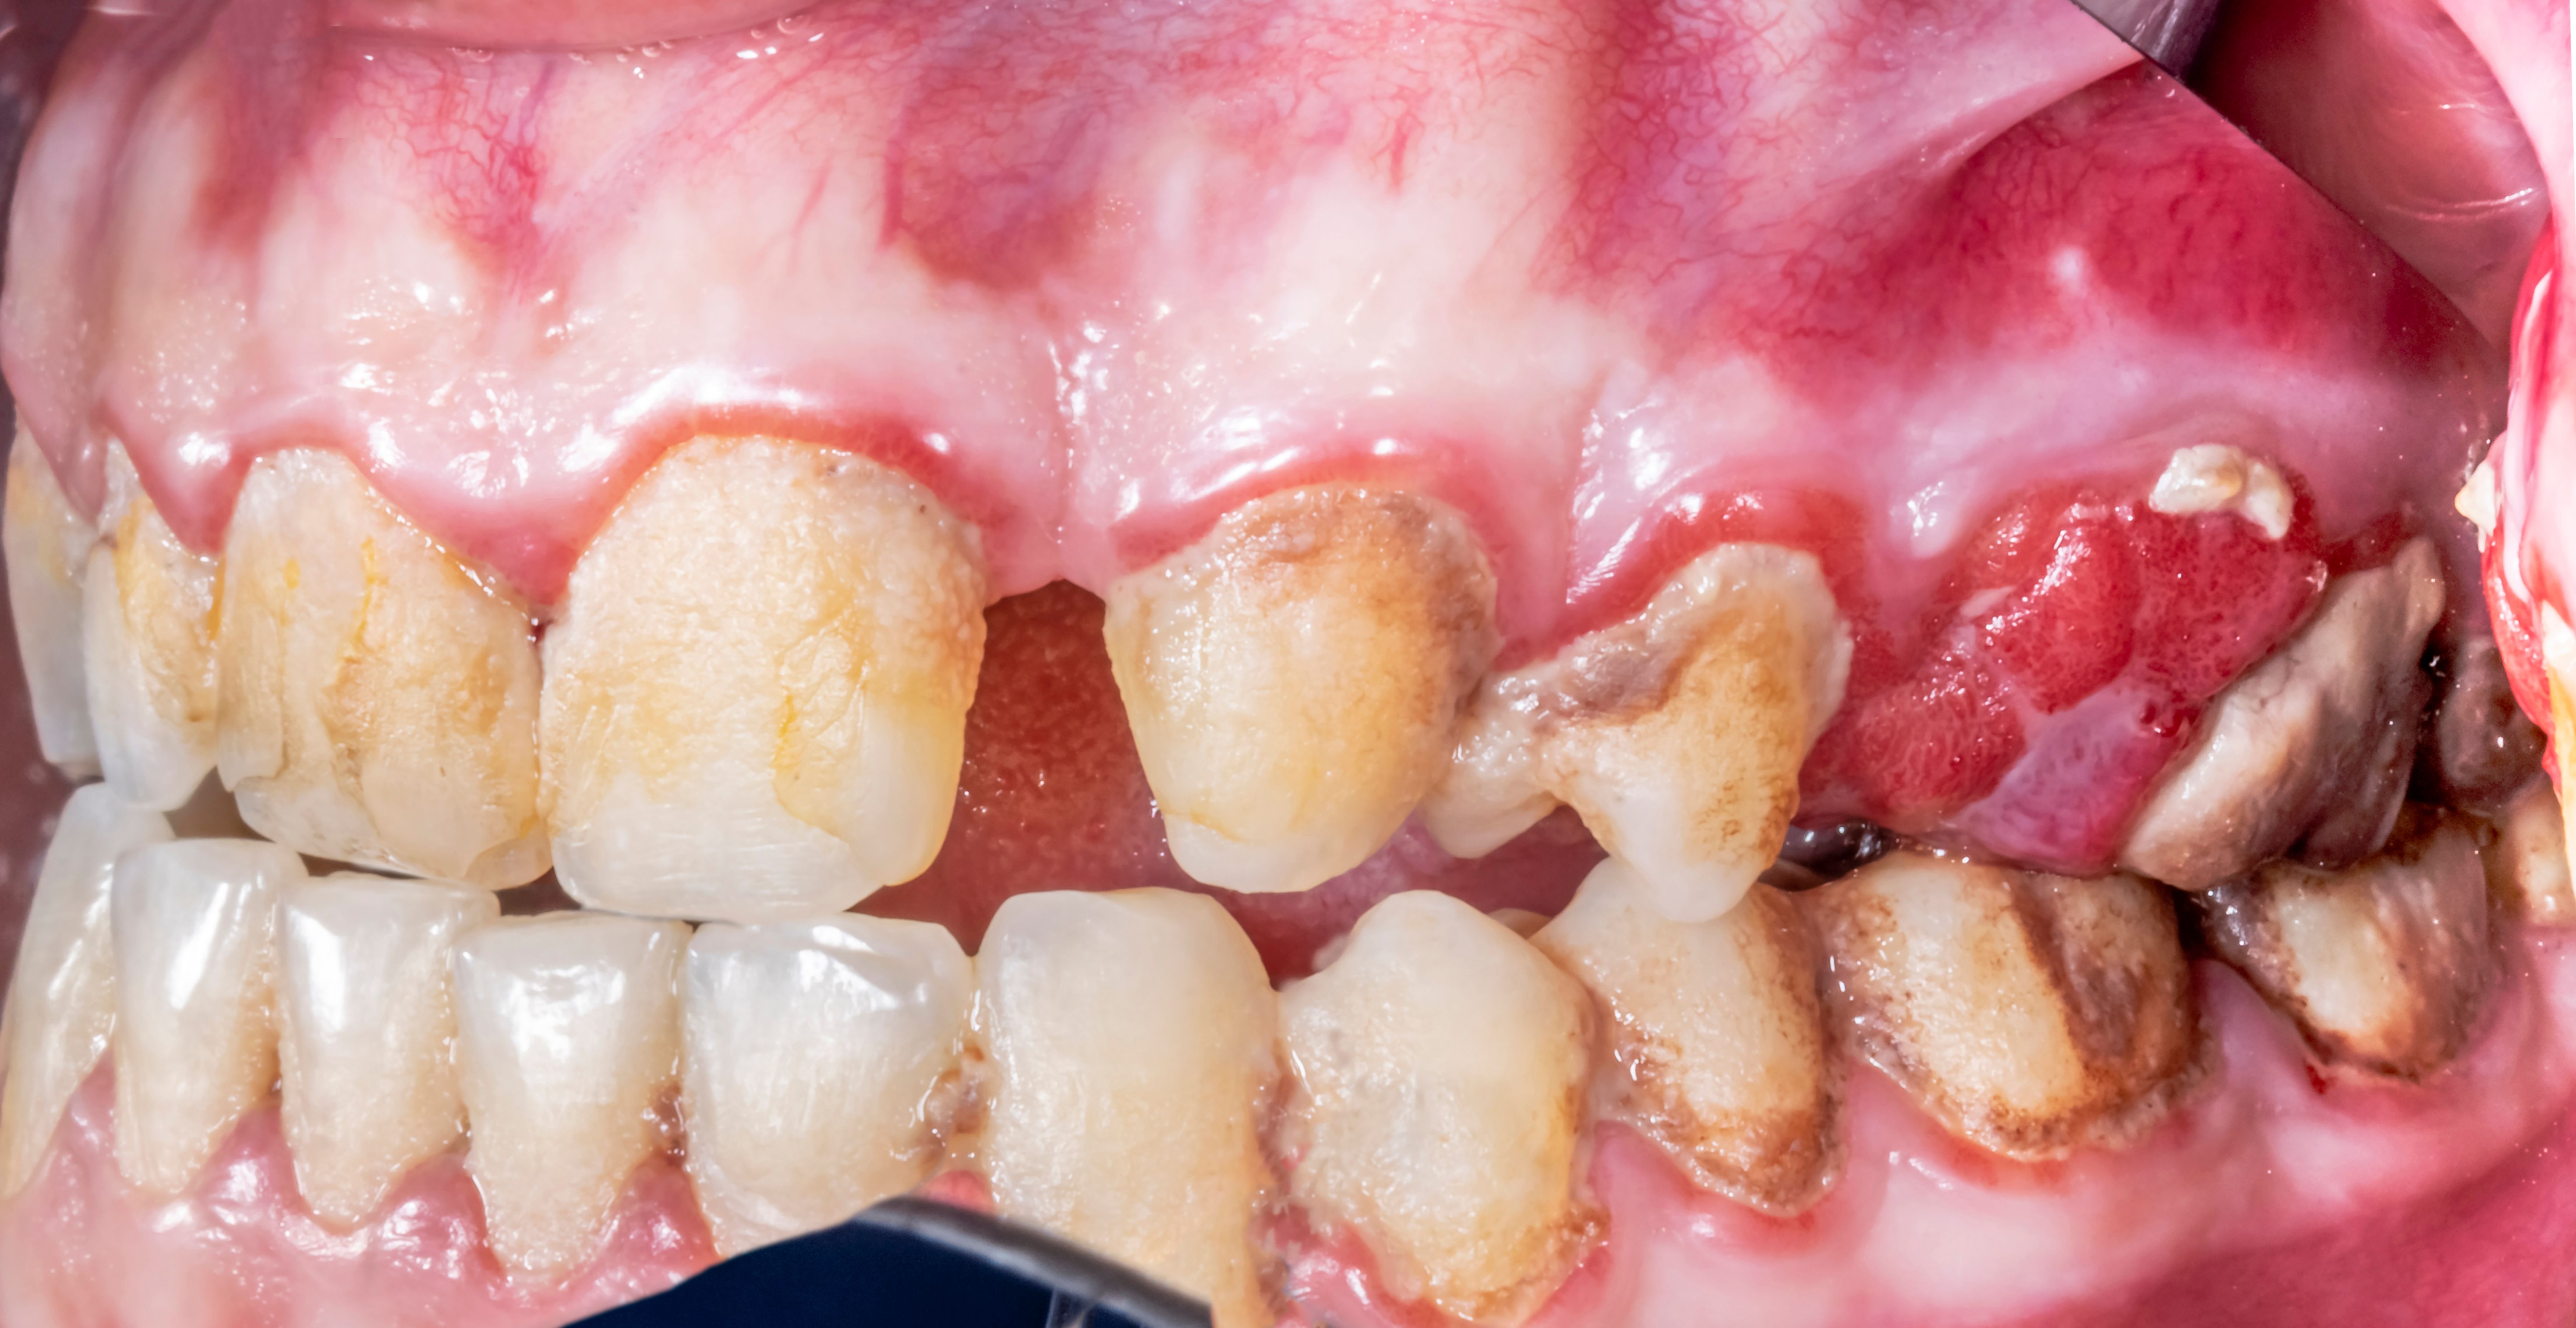

Early detection of gum disease can prevent severe complications. Some common symptoms include:

- Red, swollen, or tender gums

- Bleeding during brushing or flossing

- Receding gums or longer appearing teeth

These symptoms indicate inflammation and possible infection in the gum tissues. If you notice any of these signs, it is important to seek dental care promptly.

The primary cause of gum disease is the buildup of plaque—a sticky film of bacteria—on the teeth and gums. When plaque is not removed through proper oral hygiene, it hardens into tartar, which can lead to more severe gum issues. Other factors contributing to gum disease include: